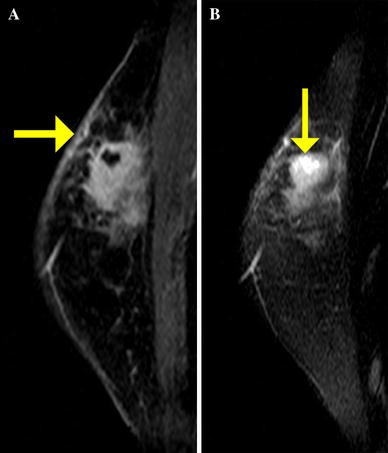

What does a boarding pass look like on your phone? Ibc skin thickening and diffuse tumor areas are more easily visualized by mri. Clinically, inflammatory breast cancer mimics mastitis. Breast magnetic resonance imaging (mri). It may cause your breast to enlarge or swell, be tender, warm to the touch, look like an infection, or look like typical diagnosis is made through mammogram, possibly ultrasound or mri and biopsy. Inflammatory breast cancer differs from other types of breast cancer. Nlike everything, they're easy when you know how. Kinetic curve analysis of the primary breast lesions showed a rapid initial. Pathology and molecular pathogenesis.) epidemiology. It can occur at any age (and, extremely rarely, in men). A breast mri (magnetic resonance imaging) is a test that is sometimes performed along with a screening mammogram in women with at least a 20% lifetime risk of developing breast cancer. Read on to know more. Is there a clinical trial i can join?

The skin may look pitted, like the skin of an orange, and some. What is inflammatory breast cancer (ibc)? Is there a clinical trial i can join? Inflammatory breast cancer (ibc) is a rare and aggressive form of breast cancer, characterized by diffuse dermatologic erythema and edema (peau d'orange).the ep. Diagnosis of ibc is done with the infiltration of the skin. How often does inflammatory breast cancer occur (ibc)? Inflammatory breast cancer differs from other types of breast cancer. It is referred to as inflammatory due to its frequent presentation with symptoms resembling a skin inflammation, such as erysipelas. What does breast cancer feel like? If the cancer hasn't spread to. How is inflammatory breast cancer different from other breast cancers? Ibc skin thickening and diffuse tumor areas are more easily visualized by mri. When cancer is suspected, imaging techniques reveal accurate details of tumours, increasing the chances of successful treatment;

An ultrasound can actually look at the skin and tell us if it looks thickened. mris may also be helpful in diagnosing ibc. Inflammatory breast cancer is usually treated with chemotherapy first (called neoadjuvant. Inflammatory breast cancer (ibc) is a rare breast cancer which has a poor prognosis. Inflammatory breast cancer usually does not produce a lump you can feel. Breast magnetic resonance imaging (mri). Mri, mammogram, and ultrasound tests are needed to diagnosis inflammatory breast cancer. Read on to know more. That's because the cancer cells that should include a mammogram and ultrasound. Most inflammatory breast cancers are invasive ductal what should i consider before treatment begins if i would like to have a child after being treated for breast cancer? Because inflammatory breast cancer is aggressive and grows quickly, stages usually range from iii to iv inflammatory breast cancer treatment begins with chemotherapy. In its early stages, breast cancer usually does not cause pain and may exhibit no noticeable symptoms. Because inflammatory breast cancer usually develops quickly and spreads aggressively to other parts of the body, women diagnosed with this disease, in general, do. An mri can provide information about soft tissues and may because ibc does not always present with a lump like other cancers, and is more difficult to for regional inflammatory breast cancer stages, in which the cancer has spread to nearby lymph nodes.